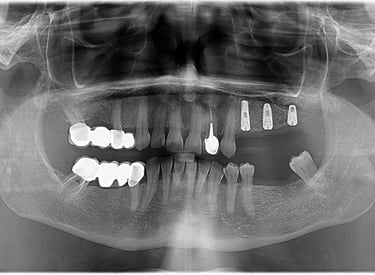

Reabilitare orala prin inserare a 3 implanturi dentare la nivelul cadranului II. In acelasi timp chirurgical s-a realizat aditie osoasa prin elevatia mucoasei sinusale in vederea asigurarii suportului osos necesar aplicarii implantului posterior.

Reabilitare implantara in cazul unor dinti restanti irecuperabili, cu mobilitate severa. Dupa extractia atraumatica a dintilor compromisi, tratamentul continua cu inserarea implanturilor dentare. In prealabil, in urma cu 6 luni s-a realizat aditie osoasa prin sinus lift extern la nivelul cadranului II, tehnica chirurgicala care ne-a permis inserarea implanturile posterioare.

Inserare 2 implanturi in cadranul III si un implant inserat post-extractional in cadranul IV